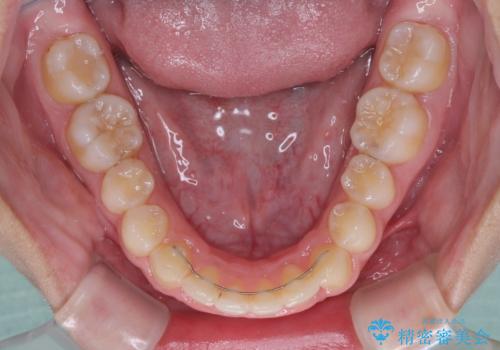

- 前歯の歯並びと不自然な色をした前歯のクラウンを気にして来院された患者様です。

上下前歯の歯列不正はインビザラインにより歯列を整え、その後に、前歯をオーダーメイドタイプのオールセラミッククラウンにて補綴治療することとしました。

前歯のデコボコを一番気にしていらっしゃいましたが、矯正治療により下顎前歯が隠れるほどのディープバイトも一緒に改善され、奥歯に負担のかかりにくい咬み合わせとなりました。